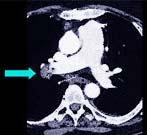

问题 该病人突发胸部疼痛,进行性呼吸困难,行X线片检查,提示右下肺病变,急诊CT平扫加增强,如图所示,则 ( )

选项 A.X线片示右下肺实变影 B.SCT增强扫描示右侧肺动脉主干完全性充盈缺损 C.右肺动脉开口处见不规则软组织密度影 D.考虑为右侧肺动脉(中央性)栓塞 E.考虑为右侧肺癌

答案 ABCD